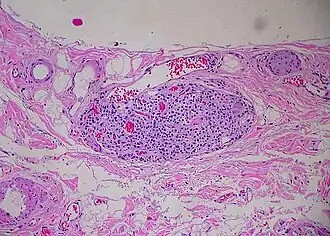

![]() Paraganglion of gallbladder | |

A paraganglion (pl. paraganglia) is a group of non-neuronal cells derived of the neural crest. They are named for being generally in close proximity to sympathetic ganglia. They are essentially of two types: (1) chromaffin or sympathetic paraganglia made of chromaffin cells and (2) nonchromaffin or parasympathetic paraganglia made of glomus cells. They are neuroendocrine cells, the former with primary endocrine functions and the latter with primary chemoreceptor functions.[1]